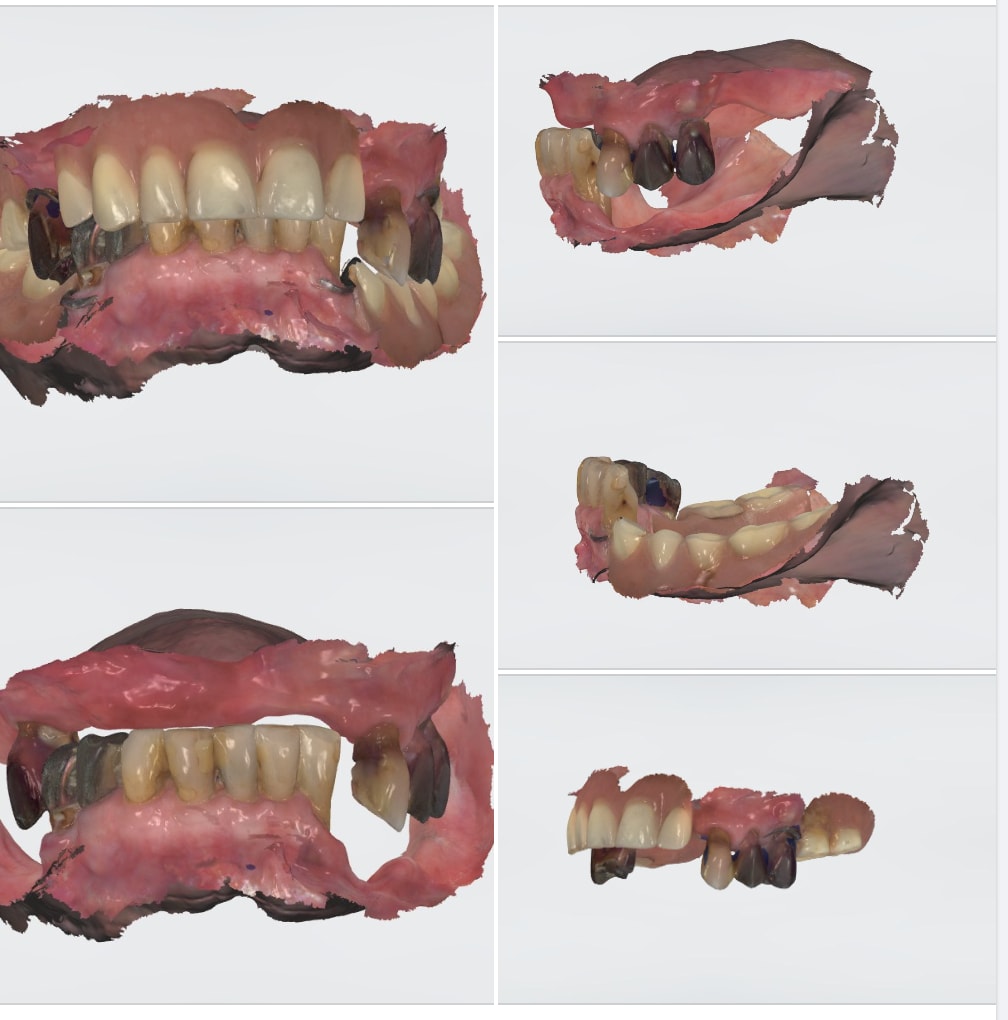

Si jamais vous vous demandiez ce que ça finit par donner ces bridges de si grande étendue qu'on vous a montré dans les précédents posts.

"Ca bouge docteur"

"Je confirme, pour bouger, ça bouge!"

PS: J'hésitais à faire une blague sur la courbe de Spee moi aussi.